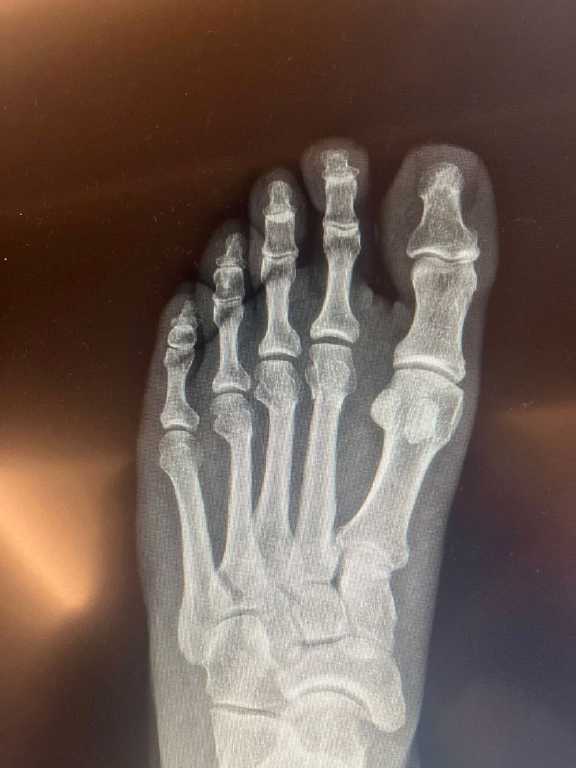

CHP Genel Başkanı Özgür Özel'in "Herkes inceleyebilir" dediği filmleri SÖZCÜ, Ortopedist Prof.Dr. Tarık Yazar'a incelettirdi.

Prof. Yazar, Özgür Özel'e ait elimizdeki röntgen filmlerini inceleyerek, "Sayın Özgür Özel'in röntgen filmlerini incelediğimizde parmak kemiklerindeki kırıkları gördüm. Açık bir yara olmaması bir şanstır. Yani, dışarıya kan akmamış. Röntgende yara olup olmadığı her zaman görülmez. Ancak, Özgür Bey'in röntgenini incelediğimizde yine de şanslı olduğunu gördüm. Biz buna 'şanslı kırık' deriz. Aslında tam kırık da diyemeyiz. Ayrılmamış, kemiğin özelliği bozulmamış. İyileşme yeteneğinin fazla olduğu bir bölgede kırık var. Şanslı tarafı kanlanmanın kuvvetli olduğu bir bölgede kırık gördüm. Bilgisayarlı tomografiyle takibi uygun olur. Tedaviye doğru başlanmış. Mutlaka iyileşecektir. Kullandığı ayak desteği gayet doğru bir seçim. Üç aya kalmaz tam iyileşme gerçekleşir. Lütfen bir daha düşmesin" ifadelerini kullandı.